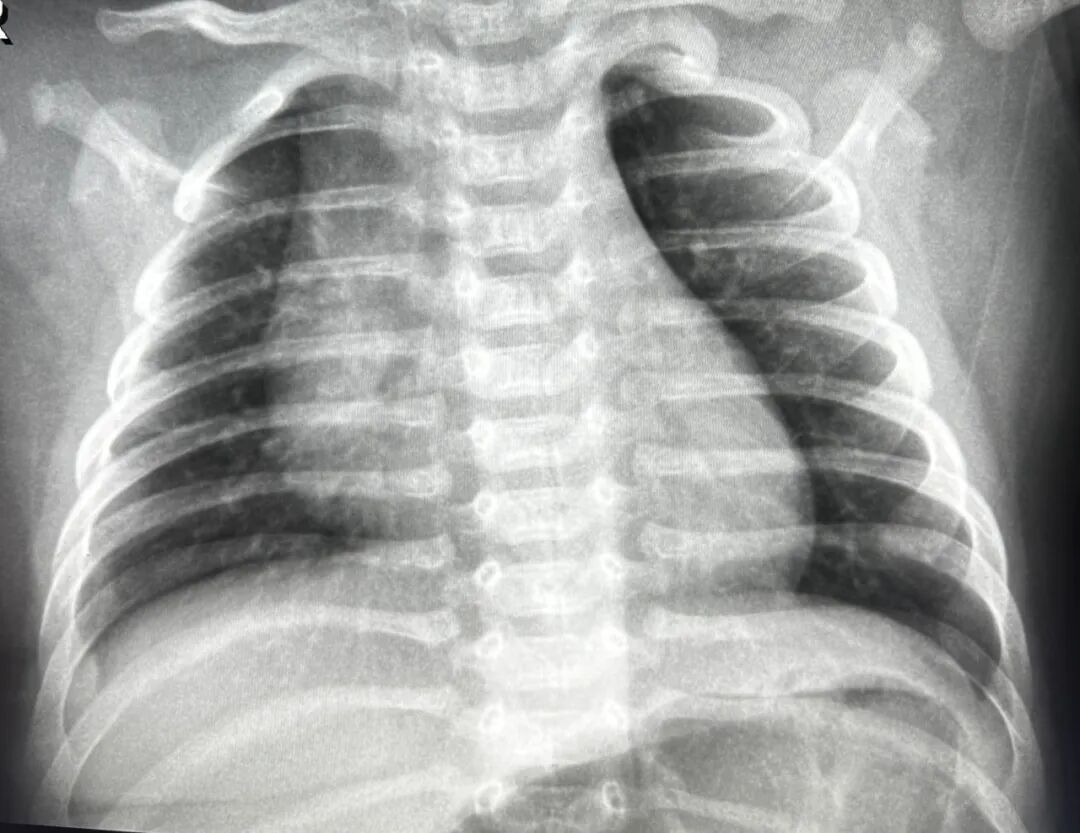

案例1、3岁的患儿平片未能明确显示肺部炎症,CT扫描显示双肺多发炎症。